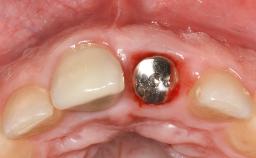

Reconstructive Treatment of a Peri-Implantitis Defect at an Implant in a Mandibular Molar Site

In this case, Mario Roccuzzo utilizes surgical bone regeneration treatment around implant 46 using a bone graft substitute and a connective tissue graft to resolve peri-implant inflammation, reduce the probing depths, and prevent further progression of disease.

A 58-year-old-male patient was referred in February 2007 for implant placement in the right mandibular molar area. Two tissue level implants were inserted at sites 44 and 46, respectively, to support a three-unit fixed dental prosthesis (FDP).